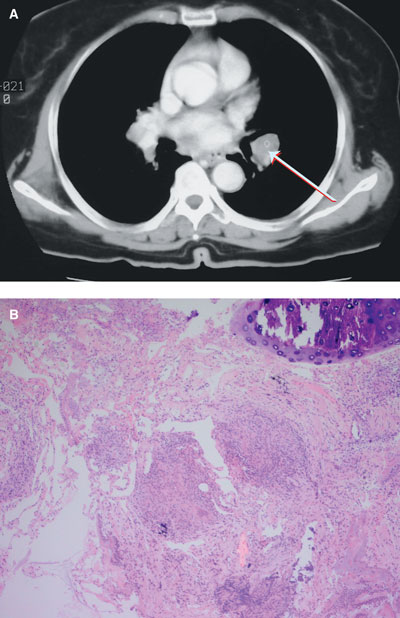

No abnormality was detected on chest x-ray or brain magnetic resonance imaging. However, a computed tomography scan of the chest showed bilateral hilar lymphadenopathy with bilateral basilar lung infiltrates (Box, A). A transbronchial biopsy revealed a single, non-caseating granuloma (Box, B).

This is an unusual case of sequential or “consecutive” bilateral facial paralysis — in which unilateral facial palsy was followed by contralateral facial palsy before the side affected first had recovered — in association with biopsy-proven pulmonary sarcoidosis. This case makes the point that a normal chest x-ray does not, unequivocally, exclude hilar lymphadenopathy.